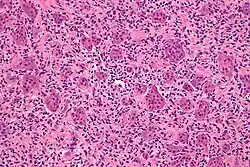

| Micrograph of a giant-cell tumor of bone showing the characteristic giant cells, H&E stain | |

The diagnosis of giant-cell tumors is based on biopsy findings. The key histomorphologic feature is, as the name of the entity suggests, (multinucleated) giant cells with up to a hundred nuclei that have prominent nucleoli. Surrounding mononuclear and small multinucleated cells have nuclei similar to those in the giant cells; this distinguishes the lesion from other osteogenic lesions which commonly have (benign) osteoclast-type giant cells. Soap-bubble appearance is a characteristic feature.